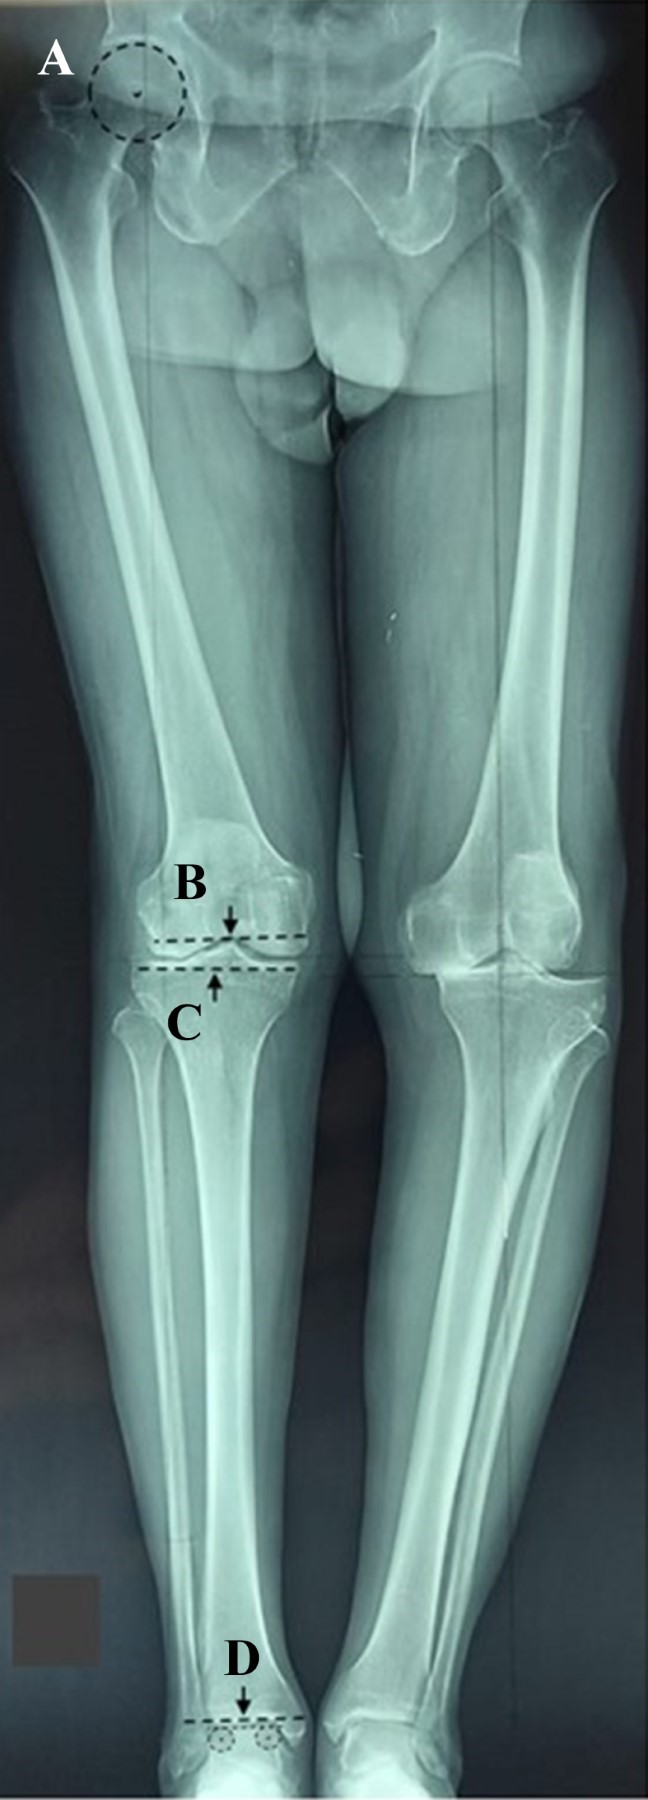

La necesidad de artroplastia total de rodilla está aumentando considerablemente y uno de los objetivos es lograr la alineación coronal postquirúrgica. La asistencia quirúrgica robótica consigue una alineación funcional, que es un ángulo cadera-rodilla-tobillo de 0°. Sin embargo, no es posible ofrecer cirugía asistida por robot a todos nuestros pacientes, por lo que debemos incluir la radiografía AP de soporte de peso de cadera a tobillo de cuerpo entero en la planificación preoperatoria para obtener una alineación de "zona segura", que es un ángulo postquirúrgico cadera-rodilla-tobillo de 0 ± 3°. ¿Cómo podemos conseguir una artroplastia total de rodilla con alineación de "zona segura" en pacientes con deformidad extraarticular?

Figura 2